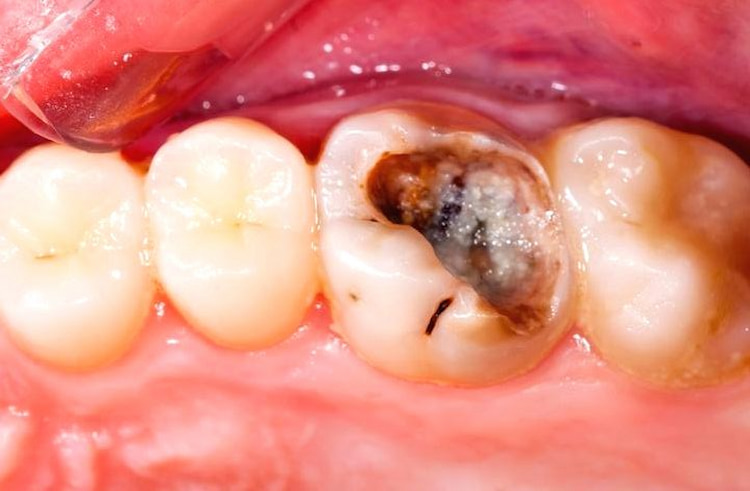

3. Dentin Decay

When decay sinks past the first layer of enamel, it begins to wear away dentin, the soft inner tooth material; cavities generally darken in color here. Most people are sensitive to sweet, hot, or cold food and drinks at this stage. We may use composite fillings or more extensive restorative work, such as inlays and crowns.

Visual Inspection of Cavities

You can sometimes spot early signs of tooth decay just by looking in the mirror. At first, cavities may appear as chalky white spots, a sign that the enamel is beginning to lose minerals. As decay progresses, these spots can turn light brown or dark brown and may form visible holes or pits on the surface of your teeth. If you notice any discoloration, rough spots, or visible damage, it’s best to book a dental appointment right away.